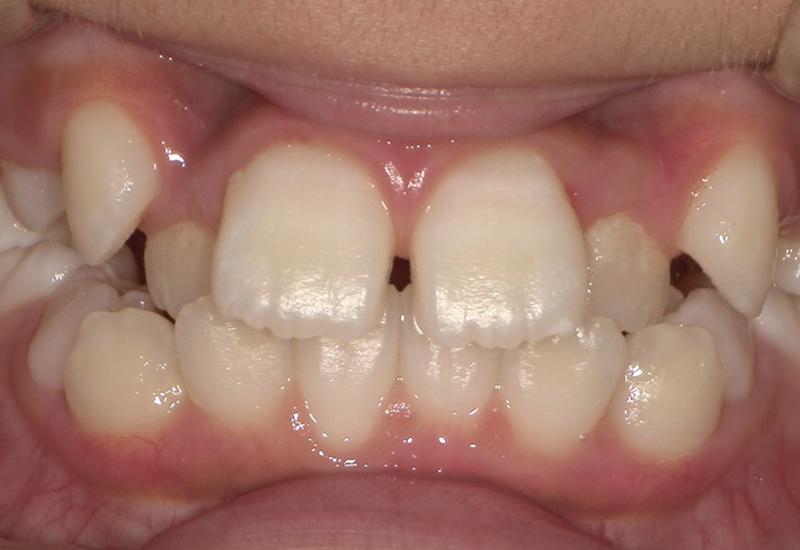

症例② シェイプメモリーアライナーによる混合歯列期の矯正

治療期間 6ヶ月

治療時の年齢/性別 10歳 / 女性

かかった治療費 440,000円

治療方法 シェイプメモリーアライナー

注意点・リスク 今、現在萌えてきている永久歯を動かす為、なるべく早く治療を終了させる